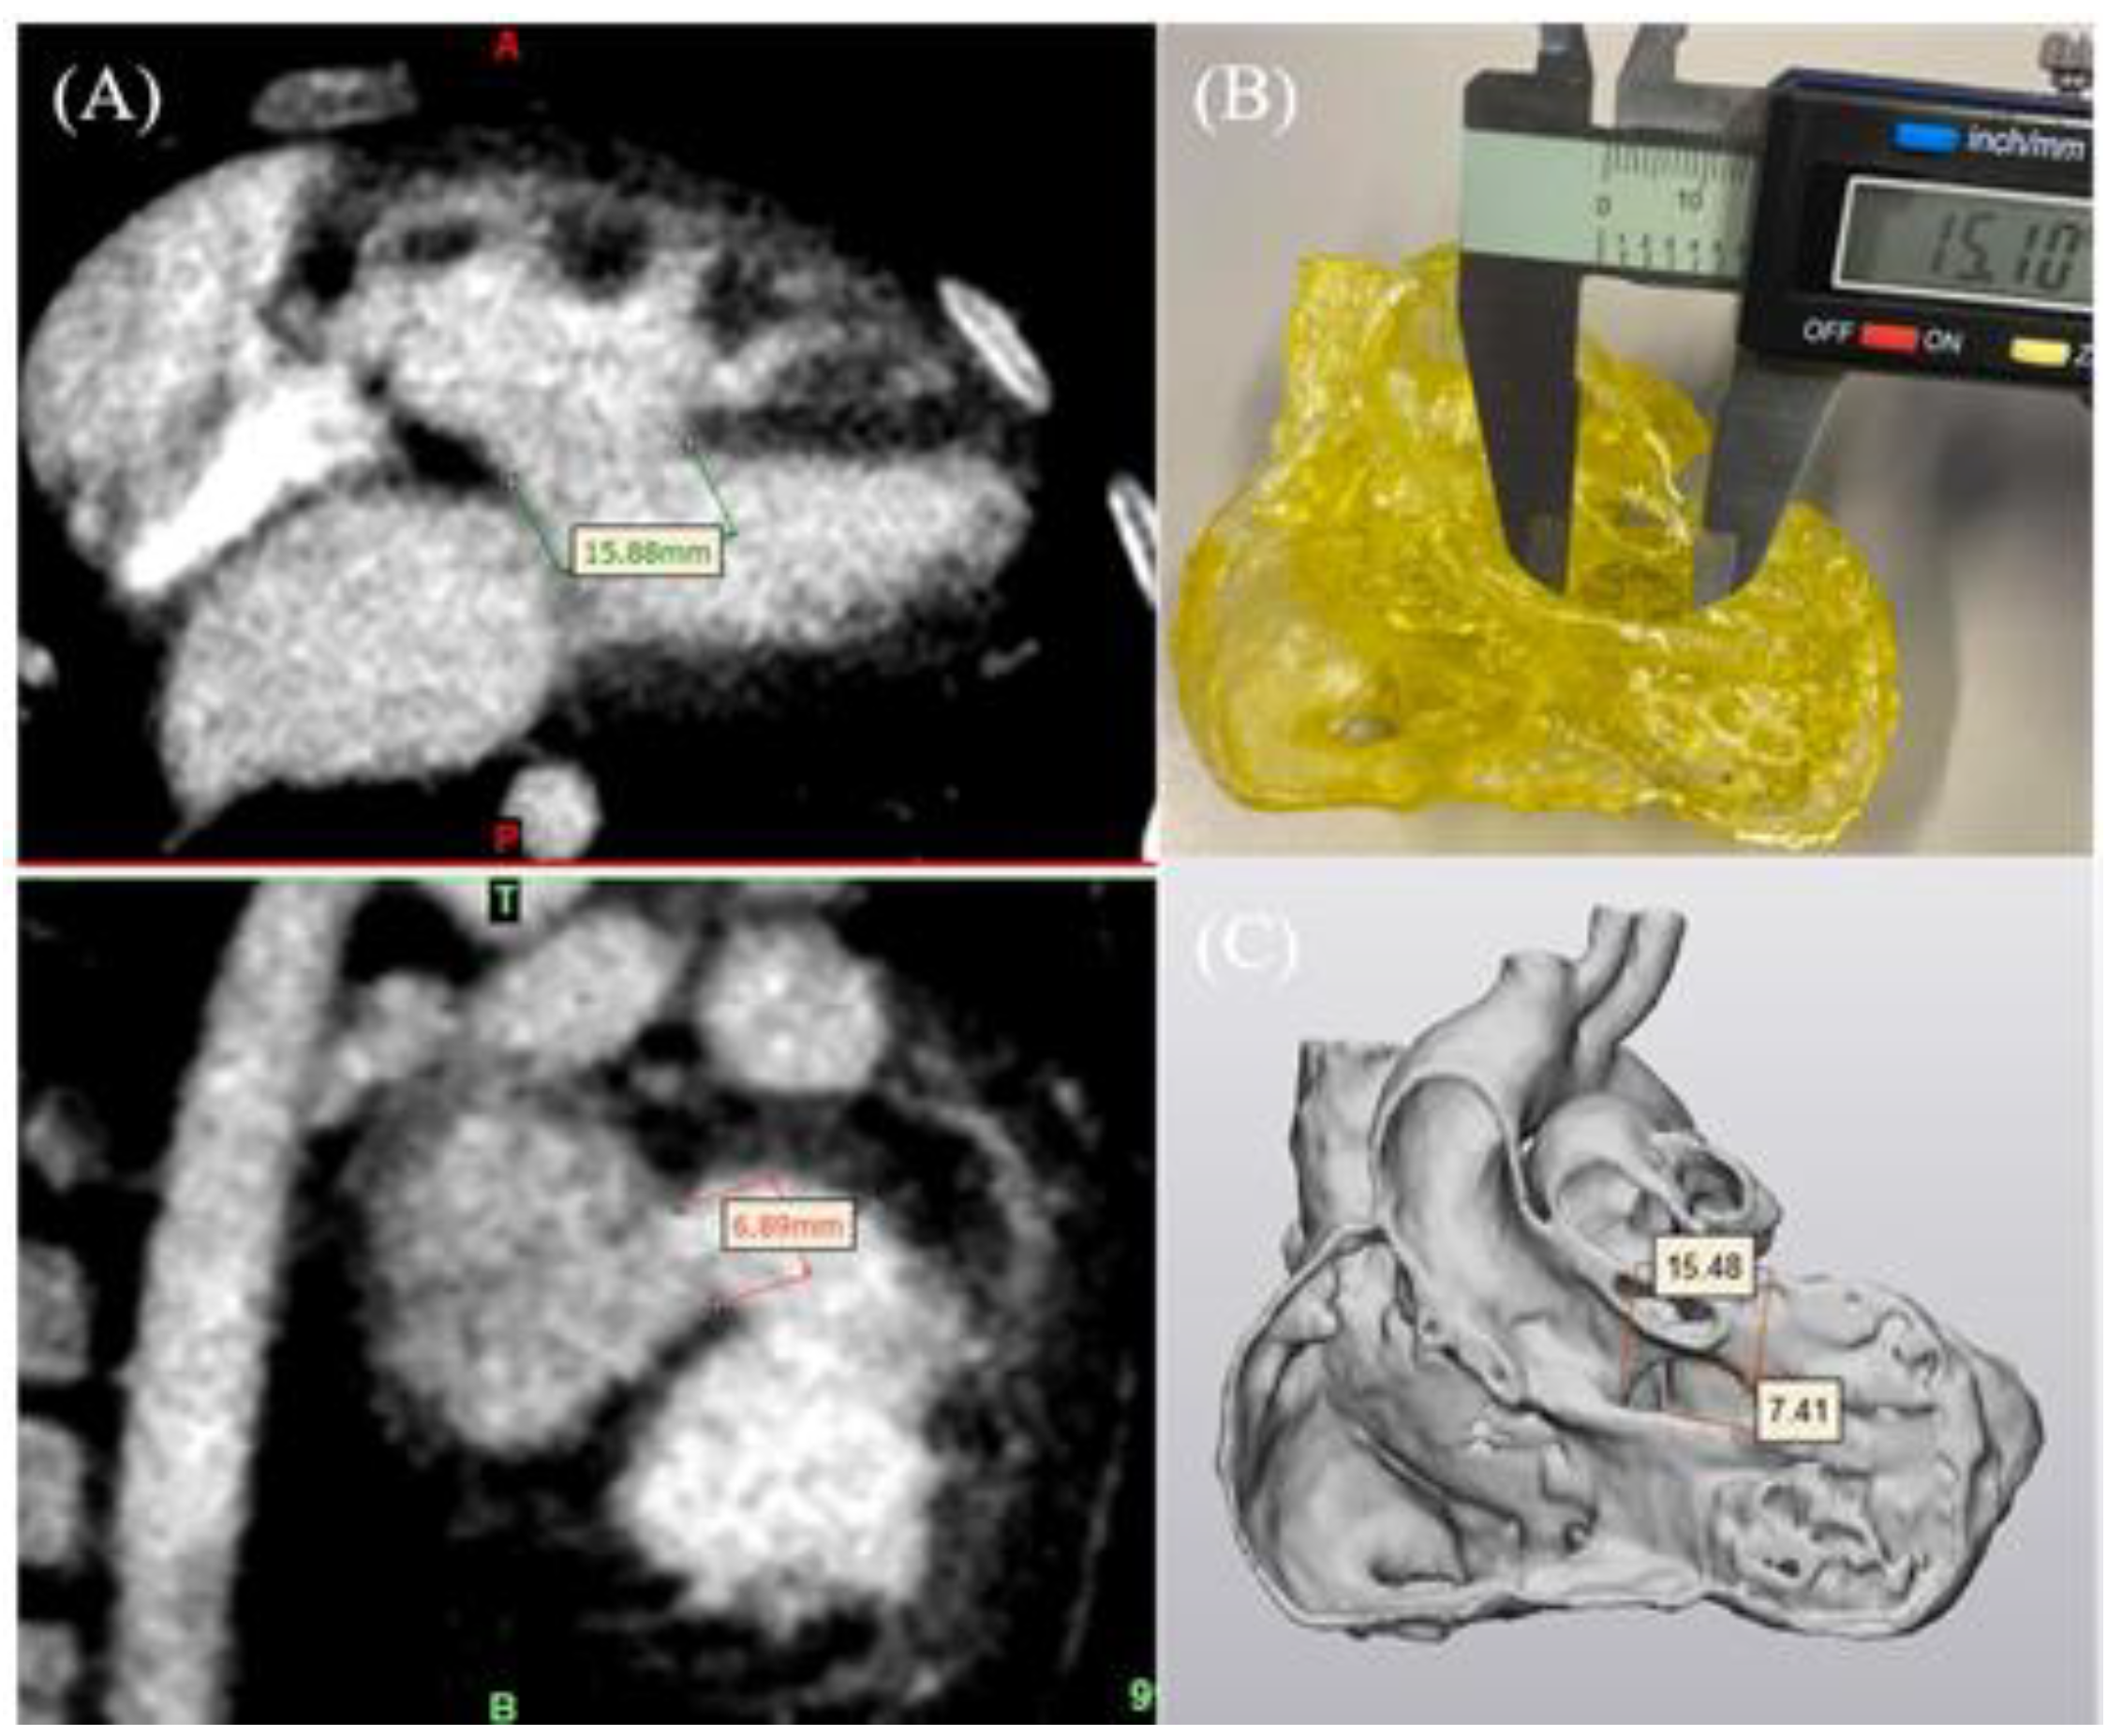

4.1. 3D-Printed CHD Model Accuracy

- Lau, I.W.W.; Liu, D.; Xu, L.; Fan, Z.; Sun, Z. Clinical value of patient-specific three-dimensional printing of congenital heart disease: Quantitative and qualitative assessments. PLoS ONE 2018, 13, e0194333. [Google Scholar] [CrossRef] [PubMed]